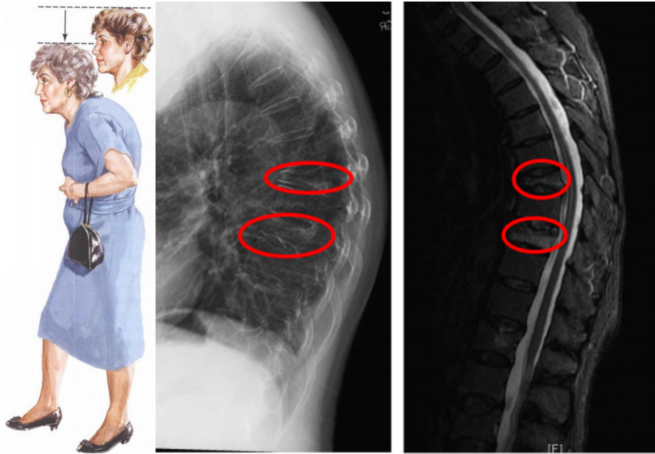

3.身高缩短、驼背

严重的椎体压缩骨折尤其是多发性椎体骨折可导致脊柱后凸畸形,患者可出现身高缩短和驼背。

脊柱压缩性骨折,胸腰椎多见,骨折主要发生在胸或腰椎移行处,以 T12最多见,其次为L1。上位胸椎也可发生,颈椎骨折几乎没有。

C.压缩性骨折:椎体各部分高度均变小。其中最常见的是楔形压缩骨折(51%),常导致患者腰背痛、脊柱后凸畸形、呼吸功能降低等一系列并发症。